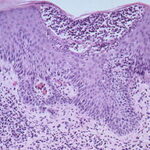

Histopathology. The earliest change consists of acantholysis in the upper epidermis, within or adjacent to the granular layer, leading to a subcorneal bulla in some instances . More commonly, enlargement of the cleft leads to detachment |

of the stratum corneum without bulla being seen. The number of acantholytic keratinocytes is usually small, often requiring a careful search to identify them. Secondary clefts may develop, leading to detachment of the epidermis in its mid level. These clefts may extend to above the basal layer, rarely giving rise to limited areas of suprabasal separation. In the setting of a subcomeal blister, dyskeratotic granular keratinocytes are diagnostic for this disorder. Eosinophilic spongiosis may be prominent with intraepidermal eosinophilic pustules. Thus, the histologic features of pemphigus foliaceus may have three pattems: {a} eosinophilic spongiosis; {b} a subcorneal blister, often with few acantholytic keratinocytes; and {c} a subcorneal blister with dyskeratotic granular keratinocytes , diagnostic of this disorder. The character of the inflammatory infiltrate is variable and depends on the age of the lesion, whether a blister is present, whether the superficial portion of the epidermis has been detached, and whether there is impetiginization or necrosis of the blister roof. |